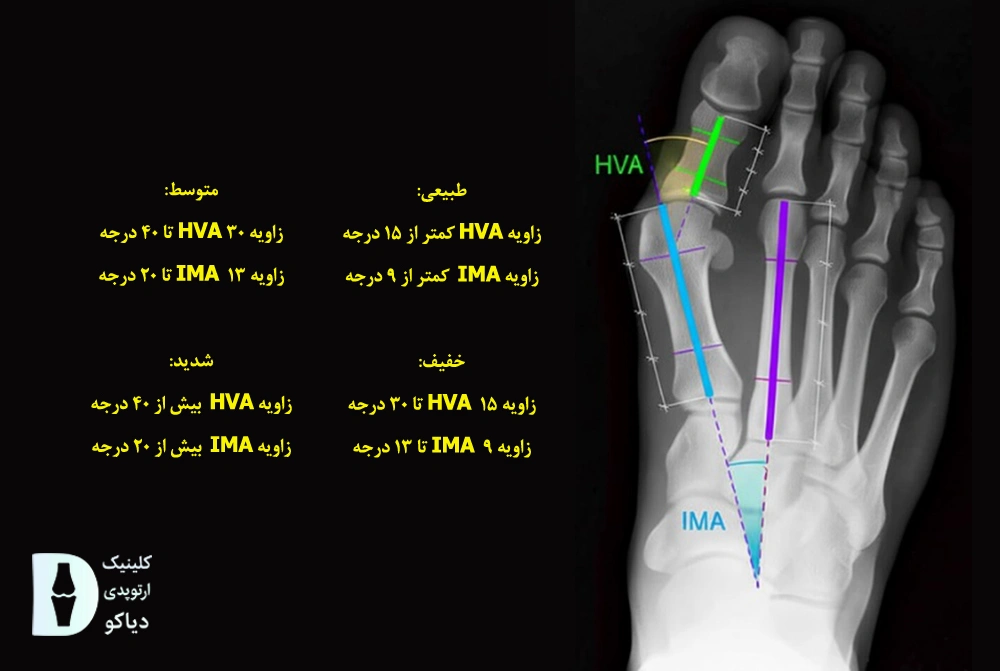

این تصویر به پزشک کمک میکند تا انحراف انگشت، وضعیت مفصل و سلامت استخوانها را بهتر بسنجد. در نهایت، شدت هالوکس والگوس معمولاً بر اساس دو زاویه HVA (زاویه هالوکس والگوس) و IMA (زاویه بین دو استخوان اصلی کف پا که زیر انگشت شست و انگشت دوم قرار دارند) تعیین میشود (منبع).